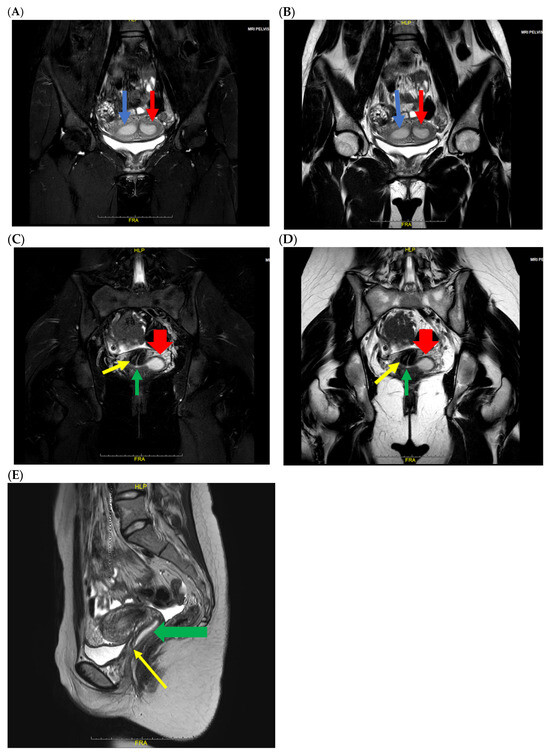

Mayer–Rokitansky–Kuster–Hauser Syndrome: From Radiological Diagnosis to Further Challenges—Review and Update

by Calin Schiau, Csaba Csutak, Anca Ileana Ciurea, Roxana Pintican, Ioana-Teofana Dulgheriu and Simona Manole

Diagnostics 2026, 16(1), 138; https://doi.org/10.3390/diagnostics16010138 - 1 Jan 2026

Mayer–Rokitansky–Küster–Hauser (MRKH) syndrome encompasses a range of Müllerian duct anomalies characterized by congenital absence of the uterus and the upper two-thirds of the vagina in young women who otherwise exhibit normal endocrine function and a 46,XX karyotype. MRKH syndrome can occur in an [...] Read more.

Mayer–Rokitansky–Küster–Hauser (MRKH) syndrome encompasses a range of Müllerian duct anomalies characterized by congenital absence of the uterus and the upper two-thirds of the vagina in young women who otherwise exhibit normal endocrine function and a 46,XX karyotype. MRKH syndrome can occur in an isolated form (type I) or in association with other congenital anomalies (type II or MURCS association), which may include renal, vertebral, auditory, and cardiac defects. It represents one of the most frequent causes of primary amenorrhea, affecting approximately 1 in every 4000–5000 women. MRKH syndrome often remains undiagnosed until a patient presents with primary amenorrhea, despite normal development of secondary sexual characteristics. Both genetic and non-genetic factors have been proposed as contributing to abnormal embryonic development, although the exact etiopathogenesis remains unclear. Imaging plays a key role in the evaluation of genital tract anomalies, allowing non-invasive and comprehensive assessment. Alongside physical examination and pelvic ultrasound, pelvic MRI is essential for identifying the presence of rudimentary uterine tissue. MRKH syndrome can have profound and lasting psychological impacts, making it essential for patients and their families to receive counseling both before and throughout treatment. A range of therapeutic options—both surgical and non-surgical—have been proposed for managing MRKH syndrome. Vaginal dilation remains the first-line treatment, as it offers high success rates with minimal risk of complications. Vaginoplasty is considered a second-line option for patients who do not respond to dilation therapy. Additionally, uterine transplantation and gestational surrogacy provide opportunities for women with MRKH syndrome to achieve biological motherhood. This review provides an updated overview of Mayer–Rokitansky–Küster–Hauser (MRKH) syndrome, encompassing its etiological, clinical, diagnostic, psychological, therapeutic, and reproductive aspects. We also present a case involving a 19-year-old woman with MRKH syndrome who presented with primary amenorrhea, highlighting the crucial role and advantages of MRI in diagnosis, differential assessment, and treatment planning. Full article